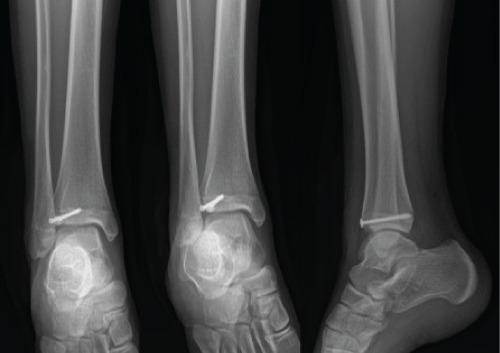

A 21-year-old female was presented in our emergency department for a painful right ankle. She had injured the ankle a day earlier while snowboarding. Examination of her ankle revealed mild pain on the range of movement, no tenderness over medial and lateral aspect of her ankle. The post injury radiographs were generally normal (Figure 5). However, her CT scan of the ankle revealed a Volkmann fracture (Figure 6).

Figure 5: Plain radiographs of the injured ankle. AP and mortise views did not show any bony injuries. (a and b) the medial clear space was less than 4 mm; (c) there was no sagittal plane instability of her ankle on lateral view.

Figure 6: CT scans revealed posterolateral avulsion fracture but no displacement was noticed and no syndesmotic incongruency.